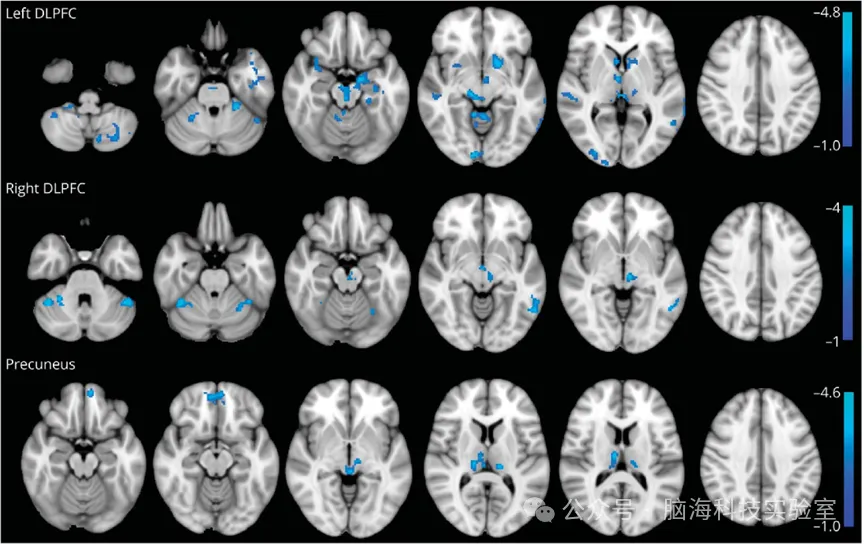

多模态脑影像数据分析平台